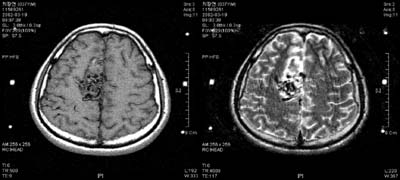

³úµ¿Á¤¸Æ

񃀁

³ú

±íÀº °÷¿¡ À§Ä¡ÇÏ¿© ³úÃâÇ÷À» ÀÏÀ¸Å² 17¼¼

¿©ÀÚȯÀÚÀÇ MRI ¹× ³úÇ÷°üÃÔ¿µ¼ú »çÁø.

³úÀÇ

±íÀº °÷¿¡ ³úµ¿Á¤¸Æ±âÇüÀÌ À§Ä¡ÇÏ¿© ¼ö¼úÀû

Ä¡·á°¡ ºÒ°¡´ÉÇÏ¿´À¸³ª °¨¸¶³ªÀÌÇÁ ½Ã¼ú

ÈÄ 24°³¿ù°¿¡ ¸ðµÎ ¿ÏÄ¡µÇ¾ú´Ù

°æ·ÃÀ»

ÁÖ¼Ò·Î ÀÔ¿øÇÑ È¯ÀÚÀÇ MRI ¹× ³úÇ÷°üÃÔ¿µ¼ú

»çÁø.

µ¿Á¤¸Æ±âÇüÀÇ

Å©±â°¡ Ä¿¼ ¼ö¼úÀÇ À§Ç輺ÀÌ ³ô¾Æ °¨¸¶³ªÀÌÇÁ¸¦

°èȹÇÏ¿´´Ù. º´º¯ÀÇ Å©±â°¡ Ä¿¼ °¨¸¶³ªÀÌÇÁ

¹æ»ç¼±¼ö¼úÀ» ¸îÂ÷·Ê¿¡ ³ª´©¾î¼ ½ÃÇàÇÏ·Á

ÇÏ¿´À¸³ª ÇÑÂ÷·ÊÀÇ °¨¸¶³ªÀÌÇÁ ½Ã¼ú ÈÄ

24°³¿ù° ¸ðµÎ ¿ÏÄ¡µÇ¾ú´Ù.